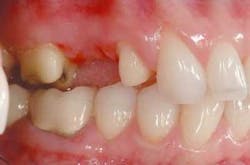

When the framework was returned to the laboratory, it was examined for fit on a master model. Initial fit was good. Small adjustments in angulations of the emergence profile were made and the facial margins were cut back for porcelain margins to increase gingival illumination. Although a ridge-lap pontic was to be utilized, the stone was relieved enough to create pontic pressure against the tissue and ensure the development of a small gingival cuff, creating the illusion of natural emergence.

The ceramic build-up was started with the application of the porcelain margin material and some highly chromatic modifiers to camouflage the substructure. These layers were fired under vacuum in a porcelain furnace to full maturity. Subsequent layers of dentin and enamel powders were built and fired to replicate the optical qualities of the patient's natural dentition. Anatomical features were built in with a porcelain brush, rather than ground in with a high-speed handpiece, to create more natural contours. Final surface texture was achieved by grinding with a 850-016 diamond bur (Brasseler), then the bridge was fired to a low glaze. A diamond-impregnated rubber polishing wheel (Brasseler) was used to smooth areas to be highlighted, and diamond polish (Brasseler) accomplished the final surface luster. The bridge was fit to a fresh solid model to verify the interproximal contacts, tissue adaptation, and occlusion, then returned to Dr. Jones for delivery.

At the framework seating appointment, the patient had only minimum sensitivity and chose not to be anesthetized. The temporary bridge was removed and the final Lava All-Ceramic System bridge was tried-in with warm water. The interproximal contacts were checked for tight or open contacts. The abutment preparation margins were checked with a 10X power surgical microscope and an explorer for any gaps or overhangs. The pontic was checked for tight tissue adaptation and the occlusion checked for even centric stops in the fossa and on marginal ridges. It was determined that there were no working or balancing interferences and no teeth out of occlusion on the bridge.